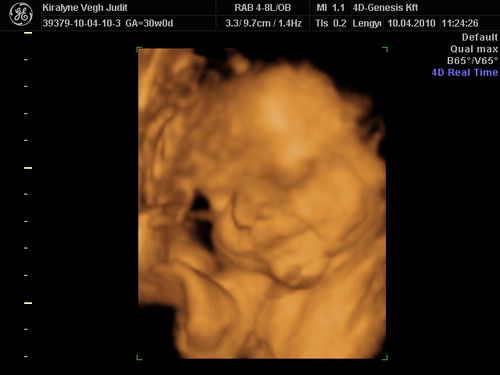

Nagyon édes a kis Izabella, tök jól sikerültek az UH képeid, nagyon fotogén a csaj!:)